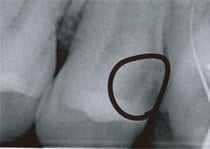

外観からはほとんどむし歯を見つけることができません。

全く症状のない大きなむし歯がレントゲンにて観察されます